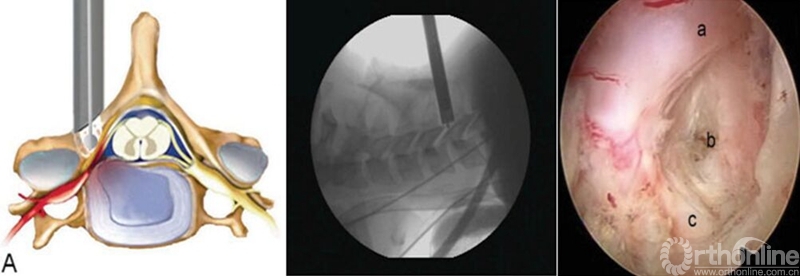

颈椎前路:与腰椎相比,颈椎由于毗邻结构复杂,穿刺风险相对较高,尤其在前路进行经皮内镜手术时更为明显。鉴于在颈椎开展经皮内镜脊髓神经损伤“零容忍”,穿刺时应特别注意技巧,即“气管投影,两指技术,皮触骨面,侧透避深。”术中透视时需找到气管侧方投影位置,然后用中指和无名指将血管鞘和内脏鞘推挤开,直至皮肤触及骨面,在两指之间穿刺入椎间隙后需透视证实未进入椎管,以确保脊髓安全。

经皮内窥镜在颈椎中的应用,有后路经椎间孔入路,前路经椎间隙和椎体两种入路。后路经椎间孔入路的适用范围主要包括C3-7神经根型颈椎病、颈椎间孔骨性狭窄,亦有部分颈椎管局限性狭窄患者可以采取后路内镜下椎管减压的手术方式。前路经椎间隙适合中央型髓核突出,经椎体用于髓核脱垂类型,不适合颈椎不稳、成角、钙化、间隙高度<4mm和严重压迫者。

颈椎后路经椎间孔入路骨性标志点为“V”点,操作时注意“靶区触骨,动力先行,显根上下,脊髓勿碰。”也就是说,建立靶区应落到V点骨性结构部分,再用动力沿V点磨除外层皮质骨,黄韧带边缘会自然显露,再用Kerrison钳扩大显露神经根肩部与腋部,用神经勾进行探查和髓核摘除,手术全程都要注意保护脊髓,避免通过后方进行椎间隙髓核摘除这一危险操作。

颈椎前路:

与颈椎后路相比,前路由于入路复杂、毗邻结构重要和颈椎解剖限制,通过前路进行髓核摘除有较大争议。对于平间隙水平的突出,可以通过经椎间隙或椎间孔进行减压操作,对于移位到椎体后缘者,可以考虑经椎体进行,但操作难度较大。颈椎前路经皮内镜手术高的围手术期并发症,以及远期疗效问题,仍然需要我们对这一入路,通过循证医学角度,来科学看待,客观分析。